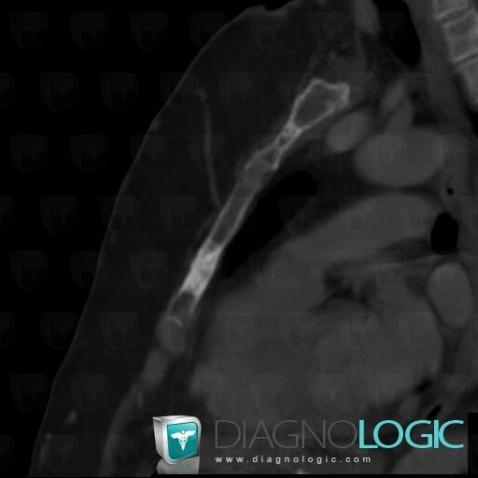

Metastasis, Sternum, CT

Here is the specific information in the key image above:

- Diagnosis Metastasis, Location(s) Sternum, with gamuts Solitary osteosclerotic bone lesion